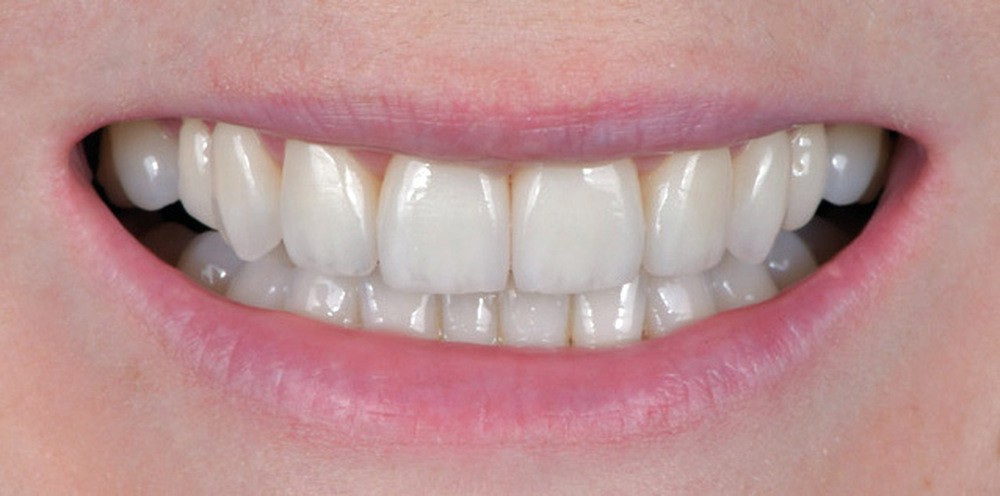

Les Drs Marie Clément et Clara Marcoux aborderont ensuite les différents apports de la dentisterie esthétique aux traitements orthodontiques. Les problèmes de dyschromies isolées ou généralisées, congénitales ou acquises seront développés ainsi que les anomalies de proportions dentaires (dents riziformes…), le maquillage (transformation d’une canine en incisive latérale…) et le remplacement des dents antérieures. Les auteurs présenteront l’intérêt du Digital Smile Design dans le diagnostic et la communication et l’arsenal thérapeutique à notre disposition pour améliorer la satisfaction de nos patients (éclaircissement, traitement des taches de l’émail, composites stratifiés, fig. 9a-d).